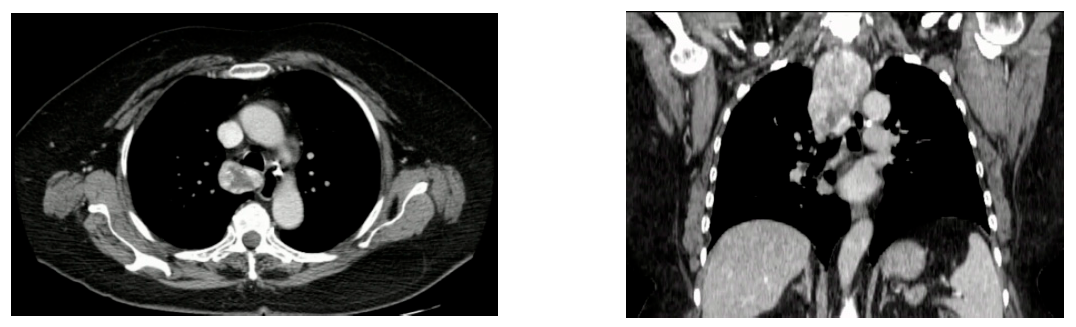

- Moschetta, M.; Ianora, A.A.S.; Testini, M.; Vacca, M.; Scardapane, A.; Angelelli, G. Multidetector computed tomography in the preoperative evaluation of retrosternal goiters: A useful procedure for patients for whom magnetic resonance imaging is contraindicated. Thyroid 2010, 20, 181–187. [Google Scholar] [CrossRef]